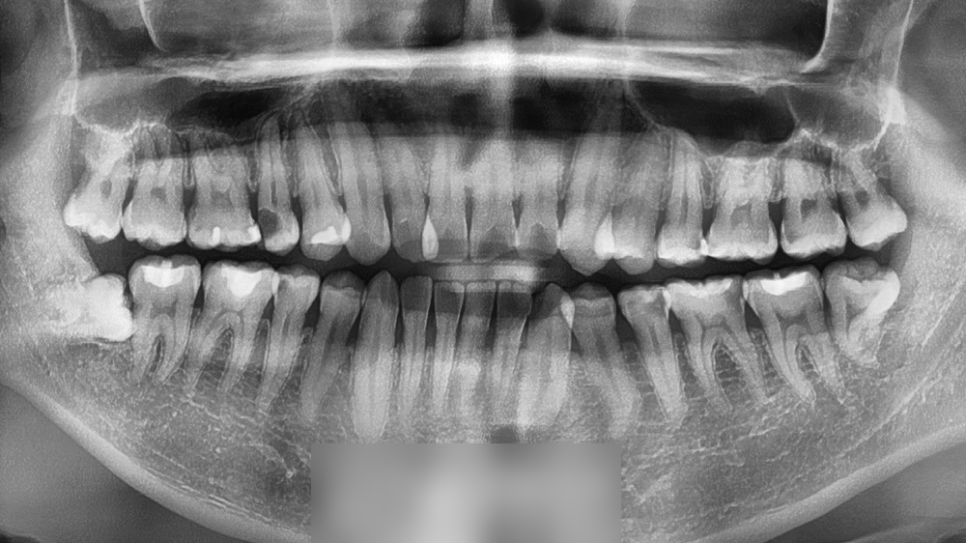

초진 사진을 확인해 본 결과

심한 총생과 반대교합 그리고

검게 썩어 있는 어금니를 볼 수 있었습니다.

삐뚤어진 배열로 인해 관리가

어려웠던 것으로 확인되는데요.

사랑니 발치와 이동을 하며 얻는

공간을 생각하면 발치는 필요하지

않겠다는 판단이 들었는데요.

따라서 비발치 전체 교정으로 계획을 세웠습니다.